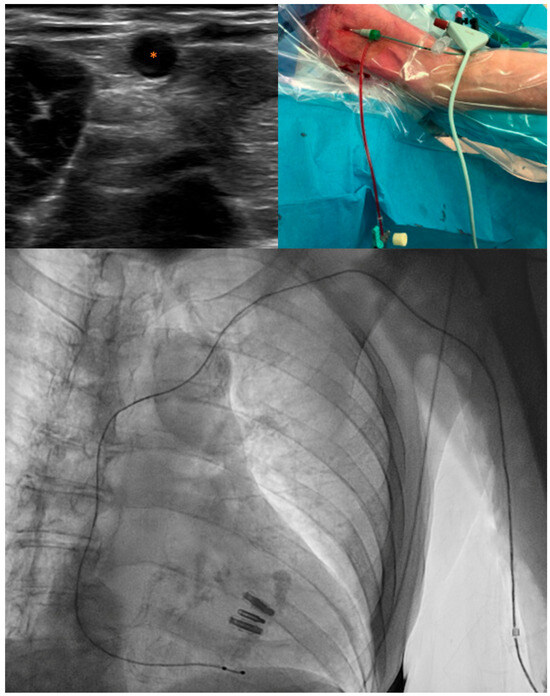

2.2. Procedure